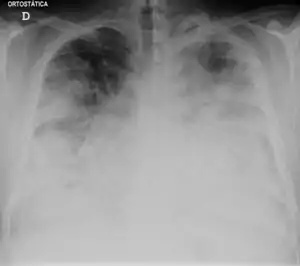

Those with Legionnaires' disease usually have fever, chills, and a cough, which may be dry or may produce sputum. Almost all experience fever, while around half have cough with sputum, and one-third cough up blood or bloody sputum. Some also have muscle aches, headache, tiredness, loss of appetite, loss of coordination, chest pain, or diarrhea and vomiting. A significant percentage of those with Legionnaires' disease have gastrointestinal symptoms, as well as neurological symptoms, including confusion and impaired cognition.[34][35]

Diagnosis

The most useful diagnostic tests detect the bacteria in coughed-up mucus, find Legionella antigens in urine samples, or allow comparison of Legionella antibody levels in two blood samples taken 3–6 weeks apart. A urine antigen test is simple, quick, and very reliable, but only detects L. pneumophila serogroup 1, which accounts for 70% of disease caused by L. pneumophila, which means use of the urine antigen test alone may miss as many as 30% of cases.[36][37][38] This test was developed by Richard Kohler in 1982.[39]